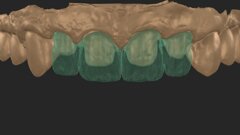

Fig. 8a: A PEEK abutment as the base for the long-term temporary restoration.

Fig. 8b: A PEEK abutment as the base for the long-term temporary restoration.

A provisional crown made of GRADIA (GC), a microceramic composite, was fabricated to achieve optimum contouring of the marginal gingiva in the highly aesthetic zone. A PEEK abutment (ZERAMEX Provisional RB; 180-day maximum period of wear), with a screw (maximum torque of 15 Ncm), acted as the base for the long-term temporary restoration (Figs. 8a & b). After eight weeks and adjusting the long-term temporary restoration in the basal area twice to optimise the emergence profile, the definitive zirconia crown (Ceramill substructure, Amann Girrbach; Creation veneer) was fixed to the customised abutment made of alumina-toughened zirconia (Figs. 9 & 10). After exact positioning (checked by probing or by taking a radiograph) the abutment is firmly fixed by utilising the VICARBO screw which is part of the ZERAMEX system. This unique screw made of carbon fibre-reinforced high-performance polymer is tightened to a torque of 25 Ncm. The final result is shown in Figure 11. The examinations after six and 12 months found no irritation of the soft tissue, and the BOI test was negative. The pink aesthetic score according to Fürhauser was 12 out of a maximum of 14 points (Figs. 12a & b).15 The process of peri-implant bone remodelling was of particular interest. Examinations were performed with periapical radiographs (right angle technique) and DBSWIN software (Dürr Dental).